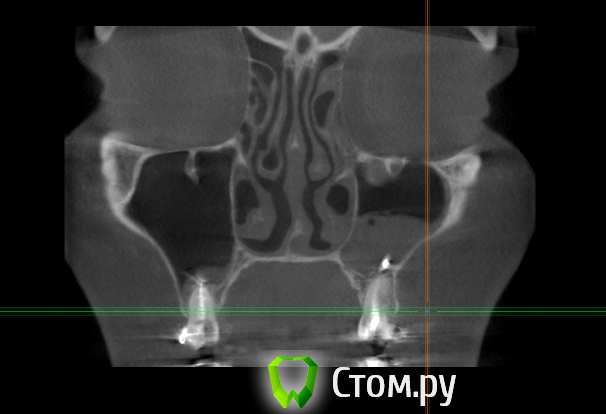

Force Опубликовано 6 апреля, 2014 Поделиться Опубликовано 6 апреля, 2014 пародонт, корни и гайморову пазуху Ссылка на комментарий

enka Опубликовано 16 апреля, 2014 Автор Поделиться Опубликовано 16 апреля, 2014 Уважаемые, ДОКТОРА! Что Вы видите на КТ? Подскажите...... Ссылка на комментарий

enka Опубликовано 22 апреля, 2014 Автор Поделиться Опубликовано 22 апреля, 2014 (изменено) Ничего меня не беспокоит ,так что подожду и понаблюдаю! Изменено 22 апреля, 2014 пользователем enka 2 Ссылка на комментарий